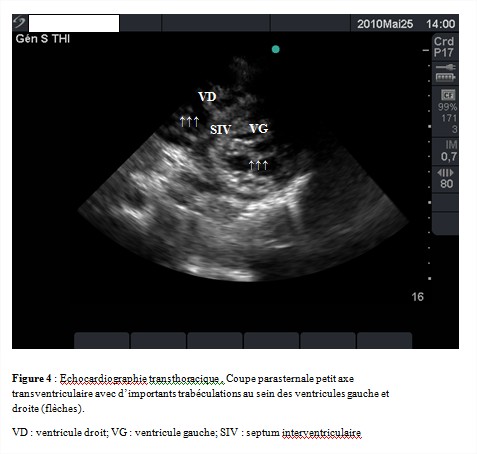

L’échocardiographie transthoracique concluait à une dilatation importante des cavités cardiaques (figure 3) (ventricule gauche en diastole = 74 mm; en systole = 67 mm; ventricule droit = 35 mm; surface de l’oreillette gauche = 34,7 cm²; surface de l’oreillette droite = 30 cm²), une hypocinésie globale des parois du ventricule gauche avec altération importante de la fonction systolique des deux ventricules (fraction d’éjection du ventricule gauche à 25 % et Tricuspid Annular Plane Systolic Excursion (TAPSE) à 7 mm). On notait la présence d’un contraste spontané intraventriculaire gauche. Le myocarde avait un aspect spongieux révélant la présence d`importantes trabéculations saillantes séparées par des cryptes localisées à l’apex et étendues à la paroi latérale du ventricule gauche (figure 3 et 4). La zone non compactée (ZNC) sous endocardique mesurait 5,5 mm contre 2,1 mm pour la zone compactée (ZC) sous épicardique (rapport ZNC/ZC = 2,61). Le Doppler couleur permettait de visualiser le remplissage intra-trabéculaire par le flux sanguin. Le ventricule droit était le siège d’importantes trabéculations saillantes séparées par des cryptes allant de l’apex à la partie moyenne de la cavité ventriculaire faisant évoquer une non-compaction du ventricule droit (figure 3 et 4). On notait également un remplissage intra-trabéculaire par le flux sanguin au Doppler couleur. Les valves étaient fines avec une insuffisance mitrale et tricuspide modérée par dilatation de l’anneau. Il existait une hypertension artérielle pulmonaire sévère avec une pression artérielle pulmonaire systolique mesurée à 69 mmHg.